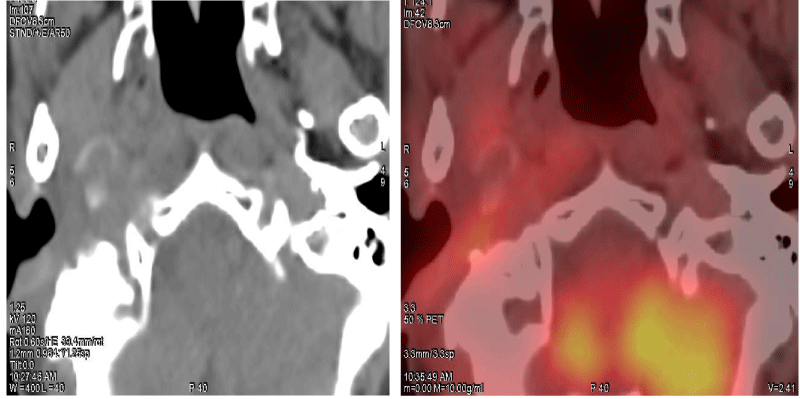

We report a case of 68 years old female with a past history of adenoid cystic carcinoma of right parotid gland post superficial parotidectomy and adjuvant radiotherapy in 2004. Now with complaints of right ear discharge and ear ache since 6 months, on further detailed and systematic evaluation, revealed a mass lesion in the EAC with extension into the infratemporal fossa (Figure 1) which was confirmed to be a well-differentiated Squamous Cell Carcinoma (SCC) on biopsy. After obtaining proper consent and ethical clearance, the patient underwent surgical de-bulking followed by adjuvant EBRT to post-operative residual disease and elective irradiation of ipsilateral nodal levels II and III using the VMAT technique (Figure 2) to a total dose of 66 Gy delivered in 33 fractions, 2 Gy per fraction. The patient tolerated radiotherapy well and was placed under regular follow-up. 12 weeks post EBRT patient was assessed clinically and radiologically with 18F-FDG whole-body PET-CT scan which showed complete morphological and metabolic response (Figure 3). The patient is under surveillance and is doing well.

Download Image

Figure 3: Post-EBRT evaluation scan (12 weeks) showing complete morphological and metabolic response.